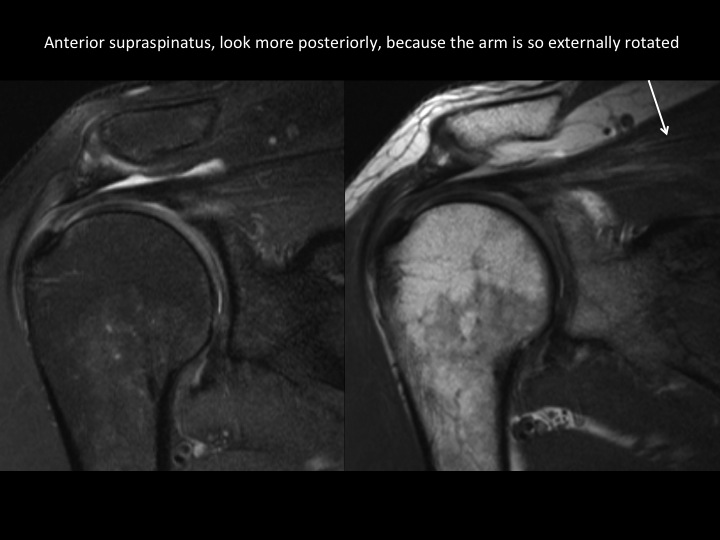

There is diffuse thinning of the suprapinatus tendon with full thickness tear posteriorly; the myotendinous jxn is retracted but there is little supraspinatus atrophy. There is a contiguous partial articular surface delaminating tear of the IST extending to the myotendinous jxn, best demonstrated in the BLO sequence. Axial images show partial articular surface delaminating tear of the subscap (note the extreme ER of the arm) with medial subluxation of the LHBT as there is a type 3 Bennett biceps pulley lesion. There is a low lying os acromiale with a subacromial enthesophyte and degen changes at the synchondrosis. Reference article.